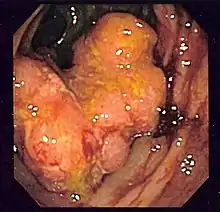

Los cánceres del intestino grueso se conocen con el nombre genérico de «cáncer colorrectal», a pesar de que hay una serie de diferencias entre el cáncer de colon y el cáncer rectal. De hecho, parece que también hay diferencias significativas entre los cánceres del colon derecho y los del colon izquierdo, cosa que ha llevado algunos investigadores a afirmar que, en realidad, son dos patologías distintas.[26]

El cáncer colorrectal es el tercer cáncer que mata más gente en el mundo, después del cáncer de pulmón y el cáncer de mama.[27] Esto es debido de no tanto a su mortalidad relativamente moderada[28] como su alta incidencia en la población. Este tumor se encuentra entre los tres más comunes en la mayoría de países desarrollados, cosa que hace que mate más gente que otros cánceres más letales pero menos comunes.

Una de las cosas que hacen que el cáncer colorrectal mate tanta gente es que a menudo es diagnosticado cuando la enfermedad ya está avanzada.[29] Como otros muchos cánceres, no suele dar síntomas hasta que ya ha metastatizado y es incurable en la gran mayoría de casos. Las autoridades sanitarias han llevado a cabo campañas de sensibilización sobre la importancia que las poblaciones de alto riesgo de cáncer colorrectal (gente de más de 45 años,[30] gente con antecedentes de este cáncer en la familia, gente con ciertas mutaciones genéticas y gente que sufre de enfermedades inflamatòries intestinales desde hace muchos años[31]) se hagan pruebas de diagnóstico periódicamente para detectar cualquier tumor antes de que se haya esparcido. Parte de este trabajo de sensibilización se ha concentrado al hacer entender a la gente que no se tiene que esperar a tener síntomas, puesto que entonces a menudo es demasiado tarde. Las pruebas más utilizadas para detectar el cáncer colorrectal son la prueba de detección de sangre en heces (más barata y fácil de hacer, pero menos eficaz)[32] y la colonoscopia, que es la estándar de referencia por el diagnóstico de este tumor.[33]